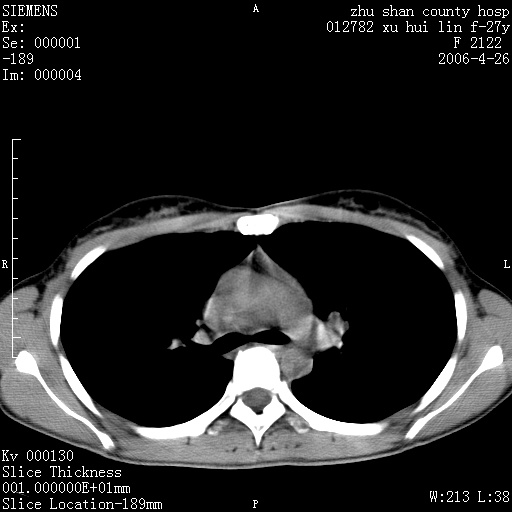

女性 病人 27岁!本院职工家属,五月前因感冒透视发现病变,ct示:左肺下叶背段感染性病变。经过半月规范抗生素治疗后复查病变无明显变化,后行四月规范抗痨治疗,复查无明显变化,后复查无效!请大家帮忙看看!

右肺下叶背段见片状高密度区,边界不清,密度不均,无钙化及空洞影,背段支气管通畅。所见层面肺门及纵隔内未见明显肿大淋巴结影。

女性 病人 27岁!本院职工家属,五月前因感冒透视发现病变,ct示:左肺下叶背段感染性病变。经过半月规范抗生素治疗后复查病变无明显变化,后行四月规范抗痨治疗,复查无明显变化,后复查无效!

诊断:首先还是考虑为慢性炎症。

机化性肺炎

病人是什么工种,从ct表现看是肺特异纤维化。

局灶机化性肺炎可能,建议她行纤支镜检查